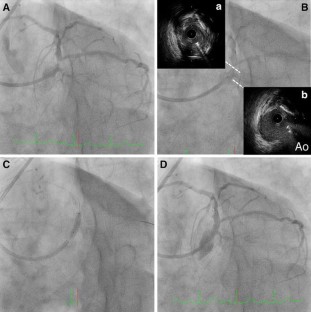

A 74-year-old man with single coronary artery and history of previous coronary artery bypass graft (CABG) was admitted to our hospital with worsening angina. Because of high risk of redo-CABG, we performed transradial percutaneous coronary intervention against the just proximal left anterior descending coronary artery (LAD) stenosis coexisting with short main trunk, anomalous right coronary artery deriving from the mid LAD and patent left internal thoracic artery-distal LAD graft. Under the guidance of IVUS, we successfully implanted an everolimus-eluting stent from the main trunk ostium to the proximal LAD without complications.

Fig. 1

Fig. 2